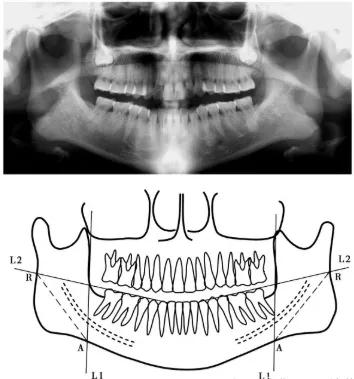

而截取多少骨量首先要考虑安全问题。下颌角的截骨量本身有一个极限值,从医学解剖结构上讲,在下颌骨里面的沿线位置,有一根下齿槽神经血管。正规医院在手术前,会借助头颅X光片和3D建模技术等,精确分析求美者面部骨骼大小和厚度、确认神经线及血管位置。

通常在下颌角手术前,需要拍摄颌骨全景片与X线头影测量片,观察下颌管的走行以及与下颌角的相对位置关系。而手术是通过下颌角截骨术目前大多经口腔内入路施行,再根据Kamishi的下颌角截骨线设计方法,在下颌曲面体层X线片上,先标出下颌骨升支前缘的垂线(L1) 与下颌骨下缘的交点(A),再标出下颌咬合平面(L2)与升支后缘交点(R),这两个交点的连线(R-A) 找到下颌角的安全截骨线。